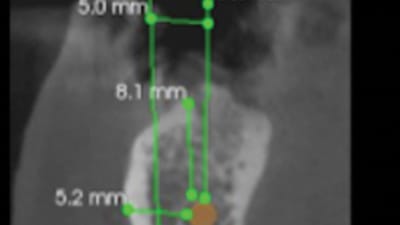

Case Series Implantology Implant Placement Lateral to the Inferior Alveolar Nerve: Selective Indications and Treatment Outcomes—A Case Series By Georges Tawil, DDS, Peter Tawil, DDSDDS, Ziad Salameh, DDS September 01, 2022 21 min read

Case Reports Endodontics The Importance of Cone-Beam Computed Tomography in Endodontic Treatment of a Mandibular Premolar With Atypical Anatomy: A Case Report By Casimiro Ricardo Oliveira Passos, DDS, Marianne de Vasconcelos Carvalho, DDS, Natália Gomes de Oliveira, DDS, Pâmella Recco Álvares, DDS, Paulo Maurício Reis de Melo Júnior, DDS, Sandra Maria Alves Sayão Maia, DDS September 01, 2022 10 min read